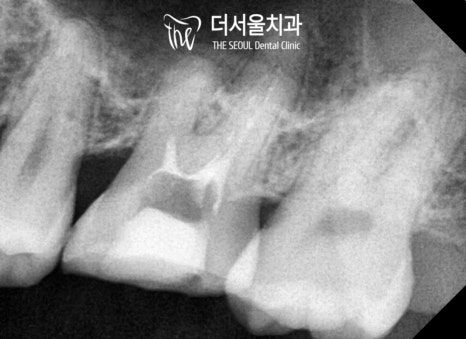

파노라마 사진을 촬영해 봤더니

눈에 띄지 않는 곳에도

치석이나 우식이 존재했습니다.

병소의 크기도 점점

줄어드는 것을 볼 수 있는데요.

다행히 성공적으로 마칠 수 있었습니다.